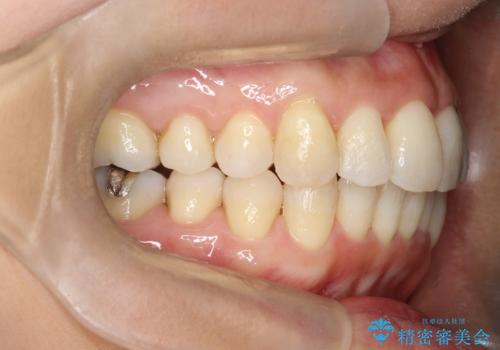

重度のガタガタのインビザラインによる非抜歯矯正

- 上下の歯のガタガタを主訴に来院されました。

インビザラインで奥歯を後方に移動させるのと、歯と歯の間をわずかに削ることでスペースを作り、歯を並べる計画としました。

しっかりとマウスピースを使用していただけたので、順調に治療を終えることができました。